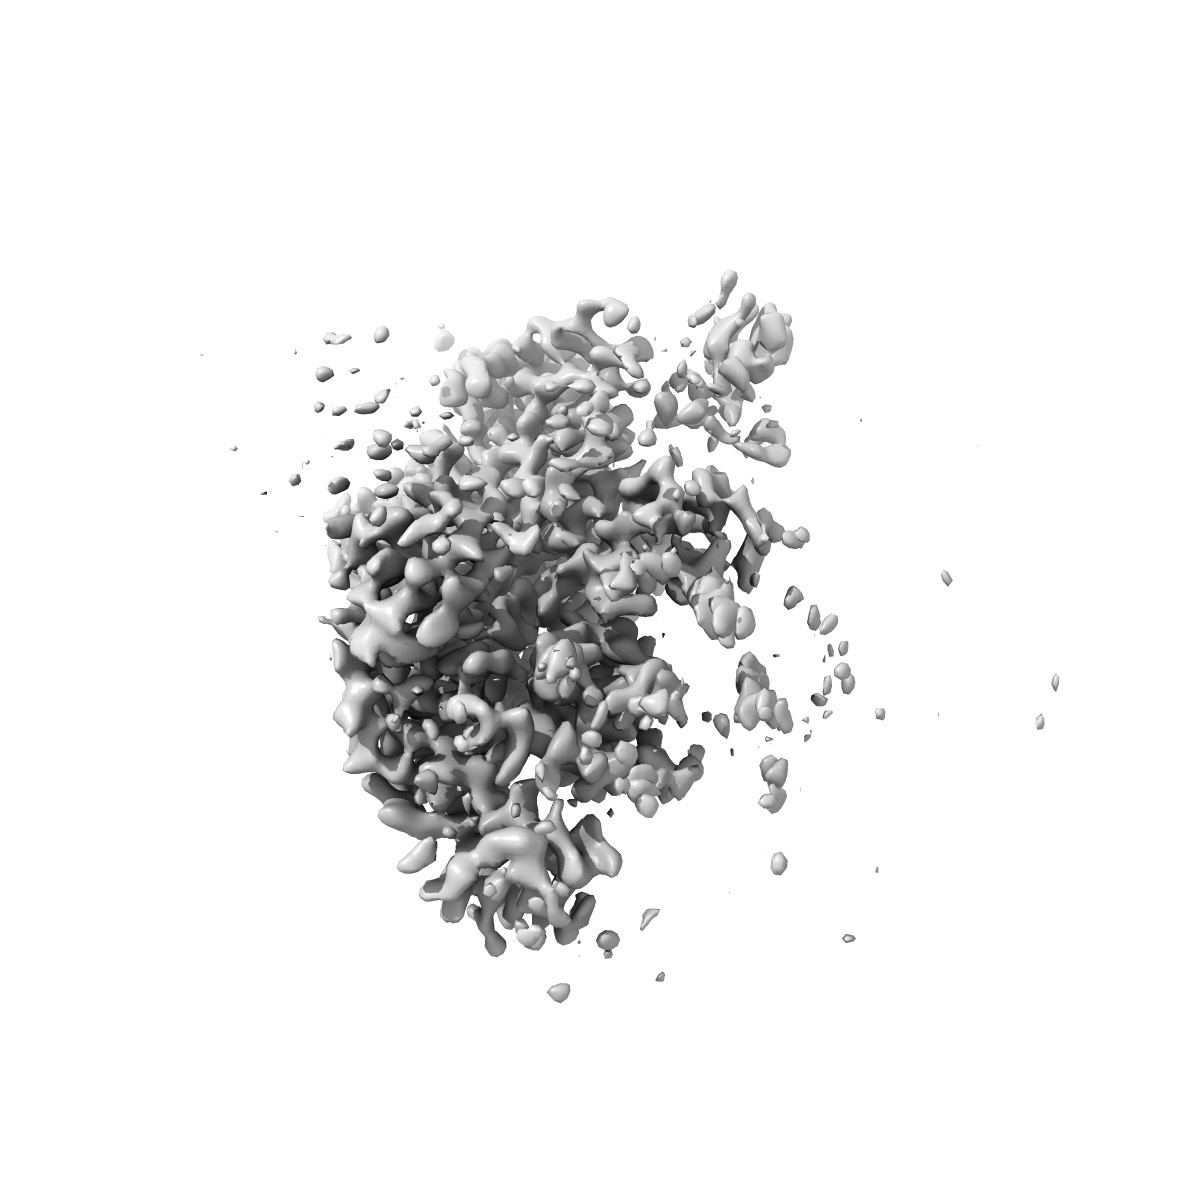

XBB-4 Fab in complex with SARS-CoV-2 BA.2.12.1 Spike Glycoprotein

Single-particle3.41 Å

Sample: XBB-4 Fab in complex with SARS-COV-2 BA.2.12.1 Spike Glycoprotein